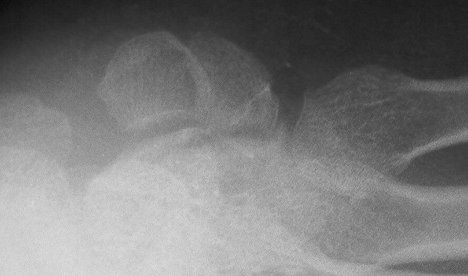

and on this slightly different angle of the same view